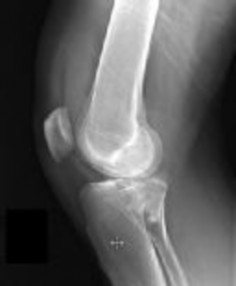

A 15-year-old male presents with deep knee pain awakening him at night. Radiographs show a permeative destructive lesion in the distal femoral metaphysis with a 'sunburst' periosteal reaction and Codman's triangle.

Biopsy confirms high-grade conventional osteosarcoma. What is the most critical prognostic factor for long-term overall survival in this patient?

Explanation

For localized high-grade osteosarcoma, the most important prognostic indicator is the histologic response to neoadjuvant chemotherapy. This is evaluated during the definitive resection. A 'good response' is typically defined as greater than 90% or 99% tumor necrosis. Patients who achieve this level of necrosis have a significantly improved disease-free and overall survival rate compared to 'poor responders' who have extensive viable tumor cells remaining.